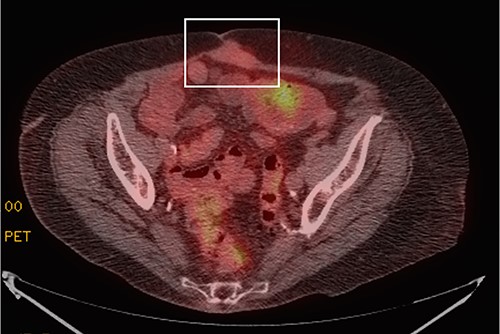

Although on surveillance, she was noted to have slow rise in CA 19-9 (58.4 units/ml) in July 2018, but she remained asymptomatic and imaging at that time showed no evidence of recurrence. In May of 2020, her CA 19-9 had risen to 477 units/ml (Fig. 1), and CT scan at that point demonstrated an umbilical mass measuring 3.8 × 2.1 cm, which in retrospect had been slowly growing over the past 2 years. Biopsy of the mass confirmed well-differentiated adenocarcinoma. Subsequent positron emission tomography (PET) scan demonstrated no other sites of recurrent disease (Fig. 2). After discussion in the multidisciplinary tumor board, she was initially offered surgery. She refused and wished to proceed with percutaneous ablation instead. However, this was not possible due to proximity of the mass to bowel. She therefore agreed to proceed with resection and this was done in July 2020. At laparotomy, the tumor was noted to be growing within the fascia and muscle of the anterior abdominal wall, and en bloc resection was completed, with subsequent repair of the fascial defect with mesh (Fig. 3). Pathology confirmed metastatic adenocarcinoma with margins of resection free of tumor.

PET scan showing a focal area of mildly FDG avid soft tissue mass within the rectus musculature deep to umbilicus abutting the midline abdominal wall (white box), measuring 3.9 × 2.0 cm, a finding suggestive of a solitary site of metastatic disease. There was no evidence of other sites of metastasis.